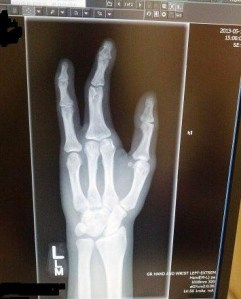

The easy thing would be to blame the resources – a variety of websites and smart phone apps – which could’ve called my attention to this gap in learning at any time. Sure, I can say “I have a spider in my pants,” but if I can’t describe how that makes me feel, what good is it? Sure, “there are three fingers on my hand” is a helpful phrase, but whether my hand just got that way or has always been two short would be a nice qualifier, no?